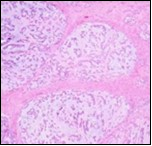

Parachordoma morphologically simulates a chordoma although tumour countenance is variable. Grossly, parachordoma depicts a firm, lobulated or nodular appearance, variable magnitude of 2 centimetres to 8 centimetres with a mean diameter of 3.5 centimetres. Tumour perimeter is well defined. Cut surface is greyish/ white, gelatinous, semi-translucent with cartilaginous zones and disseminated foci of myxoid material 5. Necrosis and haemorrhage may be absent although enlarged neoplasms are associated with focal haemorrhage, necrosis and cystic degeneration. Cogent tissue specimen obtained exhibits a tumour composed of nests and cords of cells with eosinophilic, clear, vacuolated cytoplasm and uniform, spherical to elliptical, hyperchromatic or bland nuclei. The neoplasm displays a reticular or trabecular pattern of evolution, intermingled with foci of myxoid, cartilaginous or hyalinised matrix.

Microscopically, a well circumscribed, un-encapsulated, multinodular neoplasm comprised of spheroidal, epithelioid or plump spindle- shaped cells is denominated with tumour cells configuring clusters, chains, nodules and whorls although a glandular architecture is typically absent. An encompassing chondromyxoid, hyaline stroma is discerned and the tumour is traversed with fibrous tissue septa 5, 6.

Three distinct cellular subtypes constitute a parachordoma. Epithelioid cells, miniature glomoid cells and spindle-shaped cells. Besides, the neoplasm has a distinctive population of cells with vacuolated cytoplasm, simulating physaliferous cells of chordoma 5.

Parachordoma is composed of aggregates, whorls and a pseudo-glandular pattern of spheroidal cells embedded within a focally myxoid, hyaline stroma, subdivided by broad, fibrous tissue septa. Foci of fresh and old haemorrhage are exemplified. Tumour necrosis or vascular invasion is usually absent. Mitotic activity is minimal and usually below < one mitosis per 20 high power fields5, 6.

Multinodular tumour architecture is constituted by miniature, uniform, elliptical or spindle-shaped cells with scanty, eosinophilic, finely vacuolated cytoplasm and miniature, regular or hyperchromatic nuclei. Myxoid tumour matrix is envelops neoplastic cells configuring cords and strands. Nuclear pleomorphism is absent. Tiny foci of necrosis with focal chondroid differentiation may ensue6. Meningo-endothelial cells, physaliferous cells, rhabdoid cells, ductal differentiation and anaplastic cellular dedifferentiation is usually absent. Myoepithelial carcinoma displays nuclear atypia, elevated mitotic rate and extensive foci of tumour necrosis5. Figure 1, Figure 2, Figure 3, Figure 4, Figure 5, Figure 6, Figure 7, Figure 8.

Figure 5.Parachordoma exhibiting nests and clusters of spheroidal cells with eosinophilic, vacuolated cytoplasm, uniform, bland nuclei and a circumscribing myxoid stroma 15.